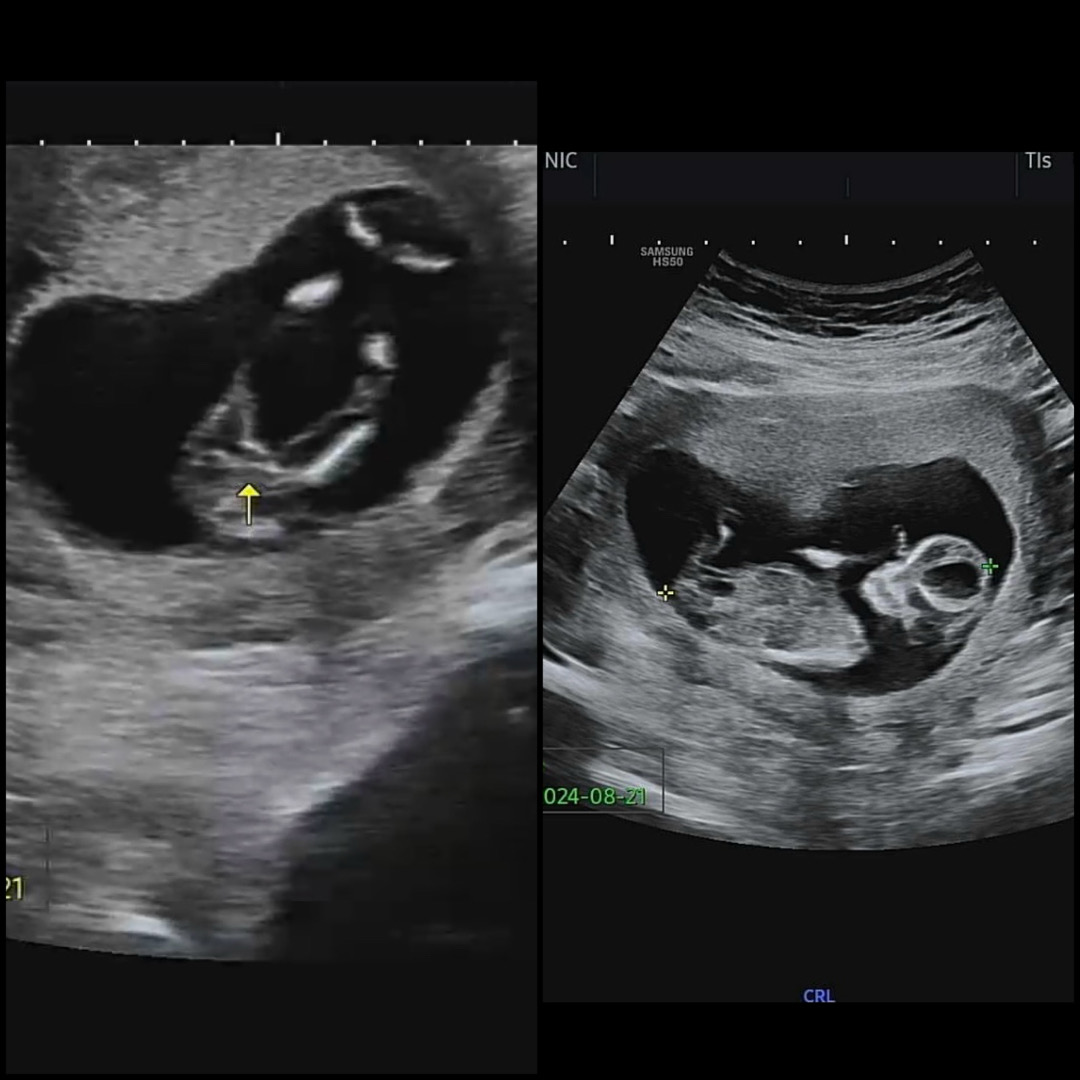

초음파 사진 봐주세용 😊

12주 5일차 입니다. 각도법, 성별문의가 엄청 많길래 저도 올려봐요 병원에서 이정도면 🌶️가 없다고 봐도 될 것 같지만 자세한 건 한달뒤에 알 수 있다네요ㅠㅠ 베동들이 보셨을 땐 딸 , 아들 뭘로 보이세요??

딸같아요 ㅎㅎㅎ 아들이면 확실하게 고환도 보이더라고요 ㅋㅋㅋㅋㅋㅋㅋㅋㅋㅋ

아 그렇다고 하더라구요… 하용이는 정말 작은 실오라기 같은 게 하나 잇는데 이게 아마 🌶️는 아닐거라는 ㅠㅠ